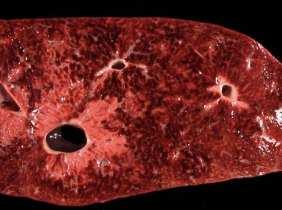

what abnormal findings may be seen on ultrasound?

-focal or diffuse increases in echogenicity

-distension of biliary tract

-focally, multifocally, or diffusely disturbed architecture

-changes in size, rounded or abnormal edges